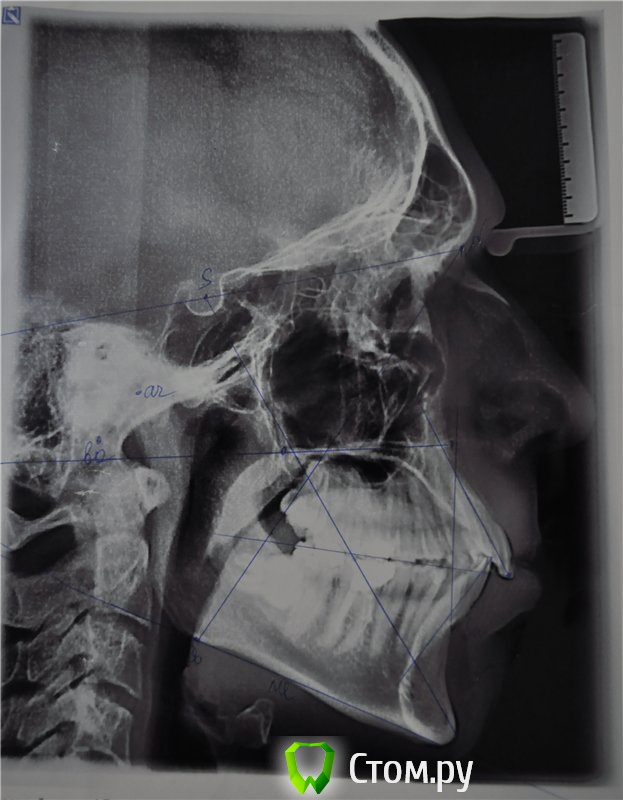

orig Опубликовано 23 февраля, 2014 Автор Поделиться Опубликовано 23 февраля, 2014 Фото до лечения покажите?фотографии до лечения нет, трг панорамный до лечения. Перед началом лечения ситуация рецесии была незначительно лучше . Ссылка на комментарий